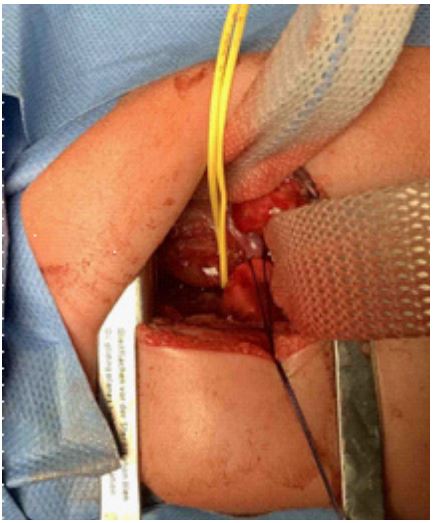

An open surgical approach using the Bianchi- transumbilical- method was chosen to create a precise access to the pylorus. Intraoperatively, the pylorus exhibited significant hypertrophic, as previously described in the ultrasound (Figure 5). A myotomy was performed, involving the removal of the hypertrophic muscle layer to eliminate the stenosis.

Figure 5: Intraoperative image of hypertrophic pyloric stenosis. Contrasting with the normal thickness of the pyloric segment (a), the distal aspect of the pylorus demonstrated uniform enlargement and thickening along its entirety (b). The surgical access followed the Bianchi technique.